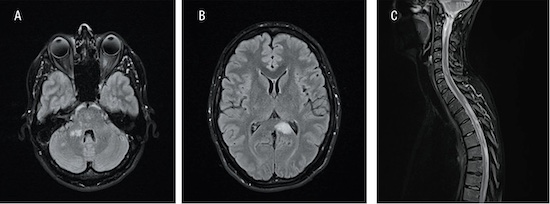

Fallbeskrivning En sars-cov-2-infektion kan ha utlöst den inflammatoriska kaskad som ledde till diagnosen MOG-antikroppssjukdom